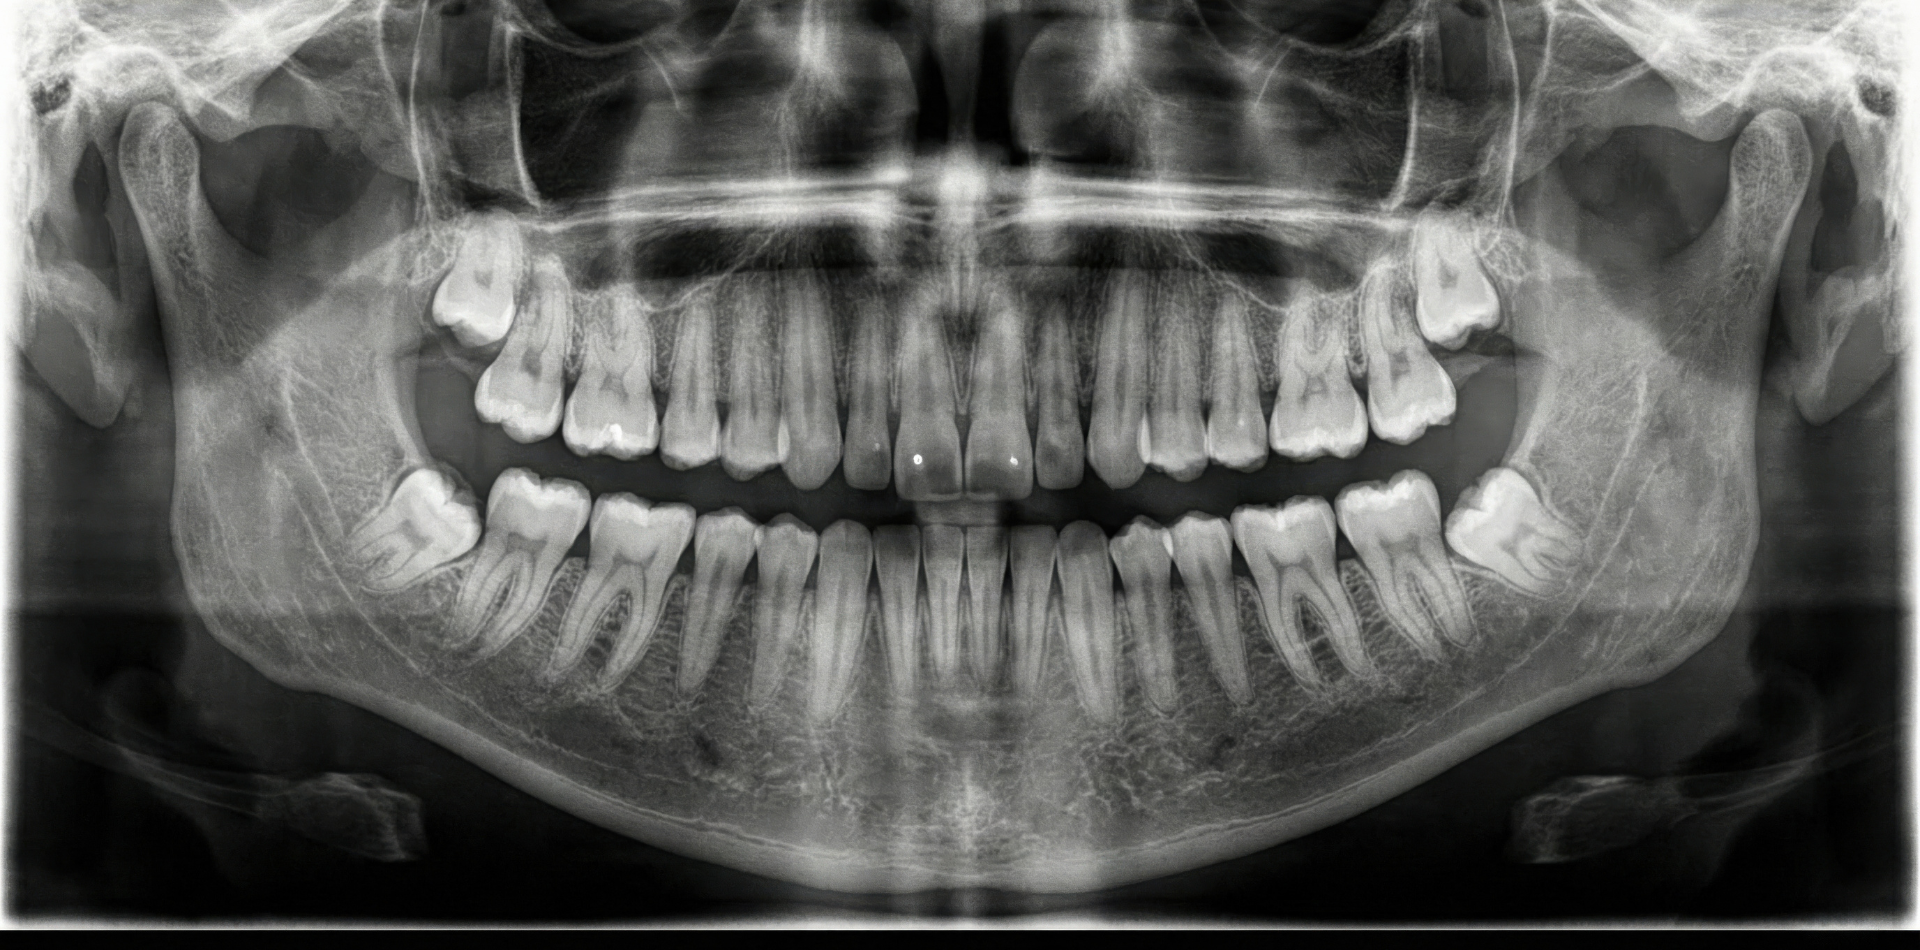

After taking the initial records – photos, xrays and measurements of your teeth – we will have a detailed consultation explaining the entire process in detail.

Full mouth rehabilitation is ideal for individuals who suffer from extensive tooth damage due to decay, trauma, grinding (bruxism), long-term neglect, or congenital conditions. Patients experiencing chronic jaw pain, difficulty chewing, frequent headaches, or severely worn teeth may benefit from this advanced restorative approach. A detailed dental examination helps determine whether this treatment is suitable for you.